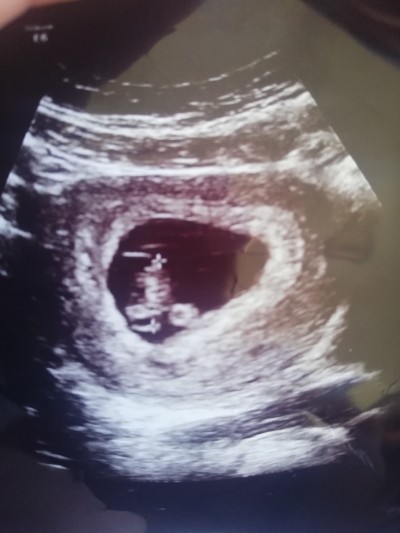

Kızlar burda 7 haftalıgım bebiş sanırım aşağıda kafası duruyor değil mi, ve sağ da mı sol da mı acaba anlayan var mı

Gebelik haftası 12. Hafta